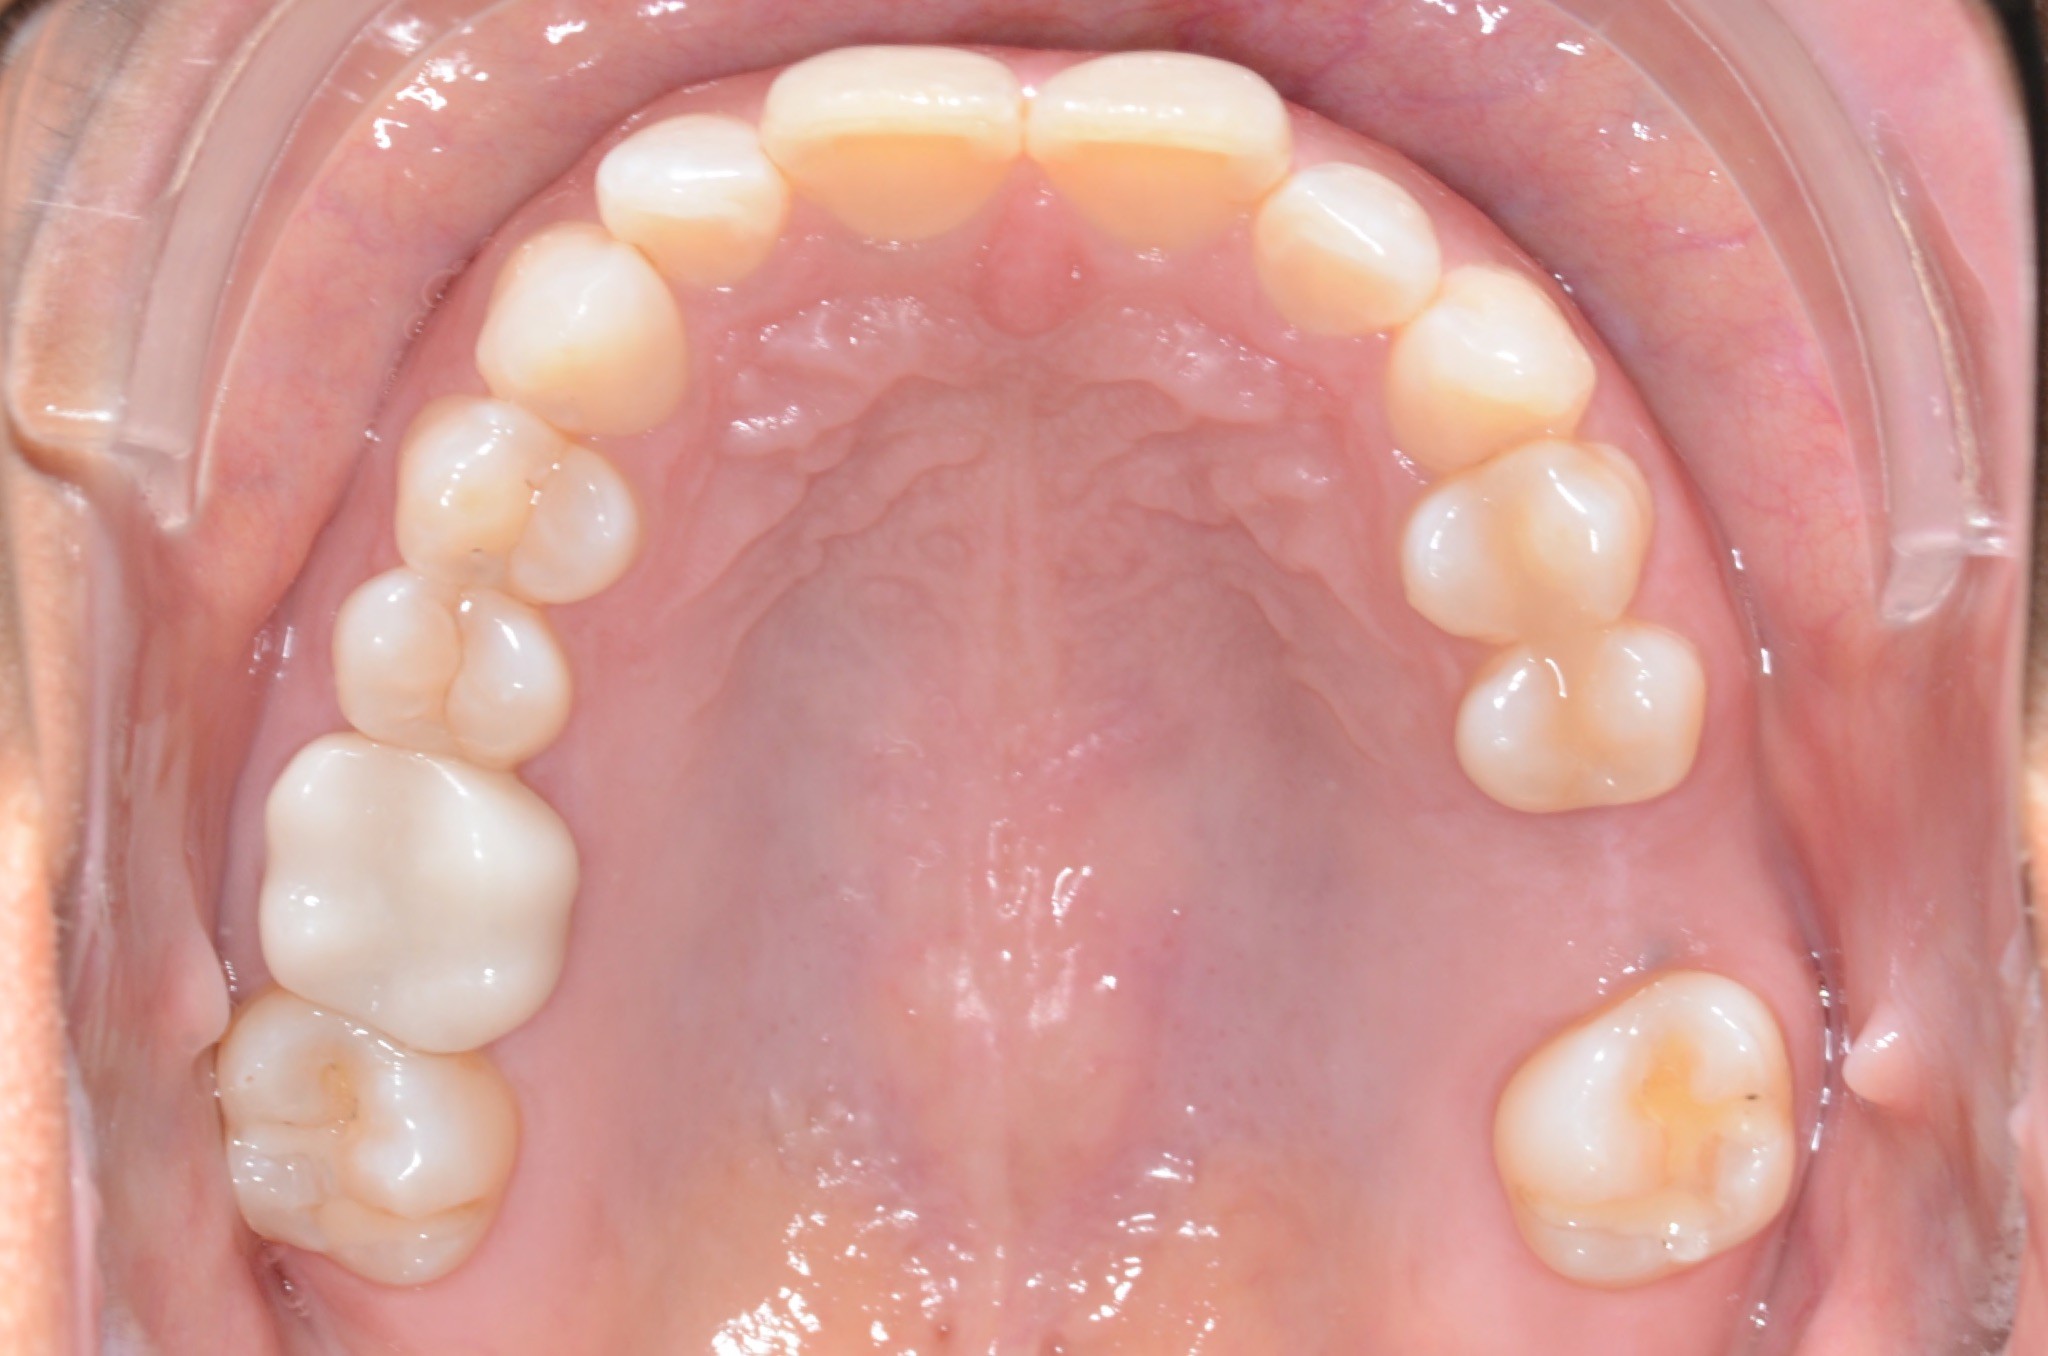

Diagnosis: Lower anterior crowding, LL3 crossbite, deep bite, missing UL6.

Adjuncts: Bite ramps, attachments, IPR

Initial treatment

INTRAORAL